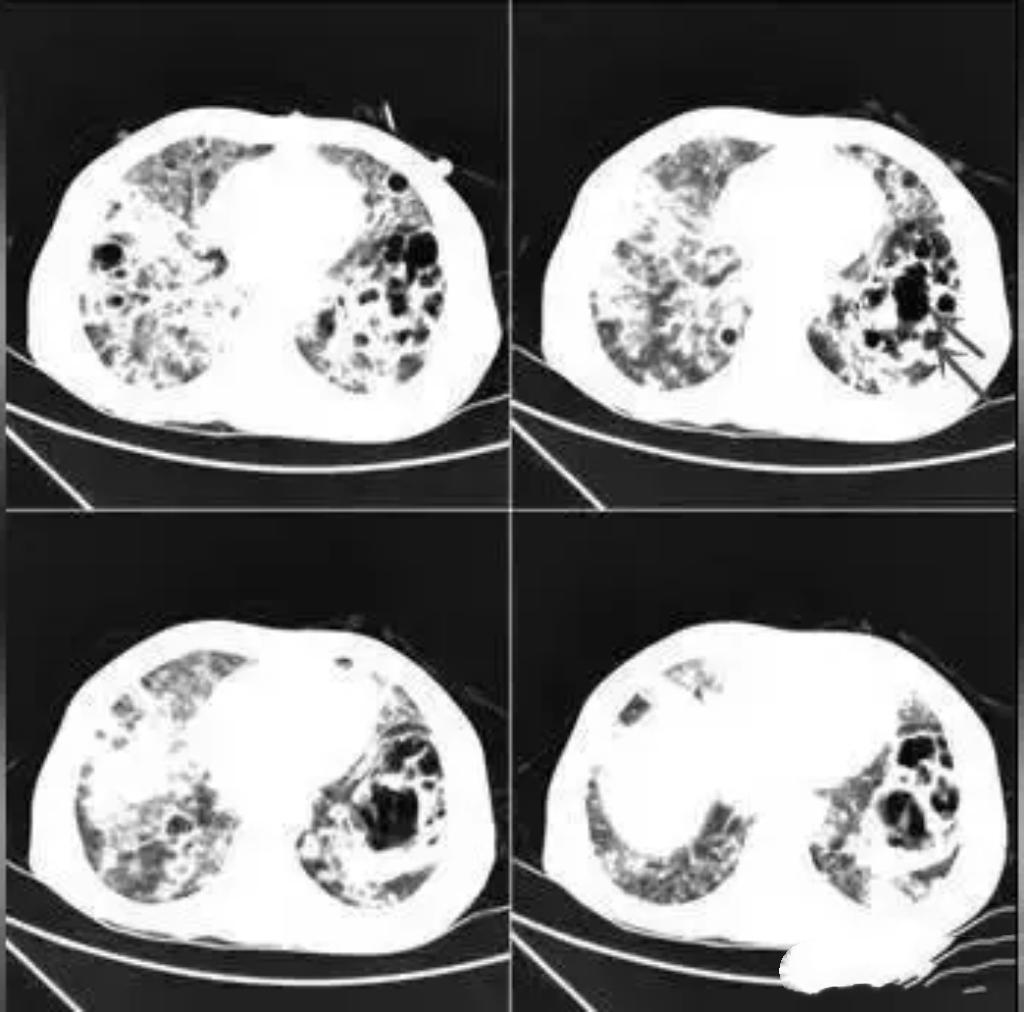

20岁男生小李长期熬夜、饮食不规律,免疫力下降,竟被结核杆菌“盯上”,肺部被“啃”出10多个空洞,咳嗽、发热、咯血等症状频发。所幸及时就医,经规范抗结核治疗,病情逐渐好转。提醒年轻人,务必重视健康,规律作息。